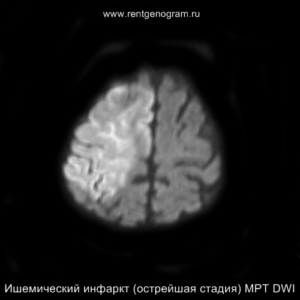

Острая фаза (первые 6 часов)

На МРТ и КТ изменения могут отсутствовать. На МРТ у некоторых пациентов могут быть первые признаки ишемии. На DWI область ишемического повреждения может быть видна через 2,5 часа после появления первых симптомов.

С 4-5 часов на DWI должны быть заметны признаки ишемического поражения, которые представляют собой «ядро» инфаркта.

Диагностика ишемического инсульта: КТ и МРТ

На остром этапе (Т2, Т1 и Flair могут сохранять нормальные результаты), на МРА можно обнаружить окклюзию артерии (при атеротромбоэмболическом и кардиоэмболическом механизмах), что будет выглядеть как отсутствие МР-сигнала от ведущей артерии (ВСА или СМА). Контрастное усиление на МРТ в остром этапе не приводит к накоплению контраста в области повреждения.

Острая фаза (6 — 24 часа)

В течение острого этапа на МРТ и КТ выявляются все морфологические признаки ишемического инсульта. Область острого ишемического инфаркта визуализируется как зона ↑Т2, ↑Flair, ↑DWI и ↓Т1 ↓ADC. Можно обнаружить тромб в артерии. На КТ в остром этапе также чётко дифференцируется поражённая область, представляющая собой участок с потерей дифференциации мозговых структур и снижением их плотности. Контрастирование в остром периоде не показывает патологических участков с накоплением контраста.